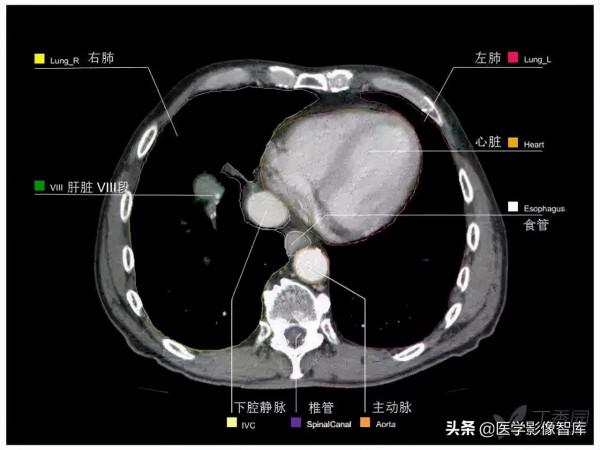

第十層:升主動脈根部水平

1. Latissimus dorsi muscle 背闊肌

2. Thoracodorsal artery 胸背動脈

3. Long thoracic nerve 胸長神經

4. Serratus anterior muscle 前鋸肌

5. Right lung 右肺

6. Crista terminalis 界嵴

7. Superior vena cava 上腔靜脈

8. Right atrium 右心房

9. Internal thoracic artery and vein 胸內動脈、靜脈

10. Right coronary artery 右冠狀動脈

11. Aortic valve 主動脈瓣

12. Sternum 胸骨

13. Conus arteriosus 動脈圓錐

14. Rib (costal cartilage) 肋骨(肋軟骨)

15. Left coronary artery 左冠狀動脈

16. Coronary sulcus 冠狀溝

17. Left ventricle 左心室

18. Left coronary artery 左冠狀動脈

19. Phrenic nerve and pericardium 膈神經和心包

20. Left lung 左肺

21. Scapula 肩胛骨

22. Intercostal muscle 肋間肌

23. Rib 肋骨

24. Right pulmonary vein 右肺靜脈

25. Left atrium 左心房

26. Trapezius muscle 斜方肌

27. Erector spinae muscle 豎脊肌

28. Thoracic vertebra 胸椎

29. Azygos vein 奇靜脈

30. Spinal cord 脊髓

31. Esophagus 食管

32. Transverse process 橫突

33. Costovertebral joint 肋椎關節

34. Thoracic duct 胸導管

35. Descending aorta 降主動脈

36. Left pulmonary vein 左肺靜脈

37. Left inferior lobar bronchus 左肺下葉支氣管

38. Bronchopulmonary lymph nodes

支氣管肺淋巴結

39. Paravertebral lymph nodes

椎旁淋巴結

40. Parasternal lymph nodes

胸骨旁淋巴結

41. Prepericardial lymph nodes

心包前淋巴結

42. Juxtaesophageal lymph nodes

食管旁淋巴結

43. Para-aortal lymph nodes

主動脈旁淋巴結

44. Intercostal lymph nodes

肋間淋巴結

Right Lung 右肺

4. Lateral segment of middle lobe

中葉外側段

5. Medial segment of middle lobe

中葉內側段

8. Anterior basal segment of lower lobe

下葉前基底段

9. Lateral basal segment of lower lobe

下葉外基底段

10. Posterior basal segment of lower lobe

下葉後基底段

Left Lung 左肺

4. Superior lingular segment

上舌段

5. Inferior lingular segment

下舌段